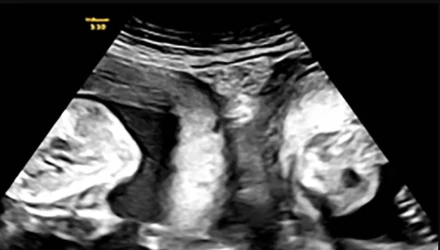

Τον Ιανουάριο, όμως, η Li έμεινε ξανά έγκυος και ανακάλυψε κατά τη διάρκεια ενός υπερηχογραφήματος ότι κυοφορούσε δίδυμα - ένα σε κάθε μήτρα και οι γιατροί του νοσοκομείου «έπεσαν» πάνω στο περιστατικό για να εξασφαλίσουν την επιτυχία της εγκυμοσύνης.